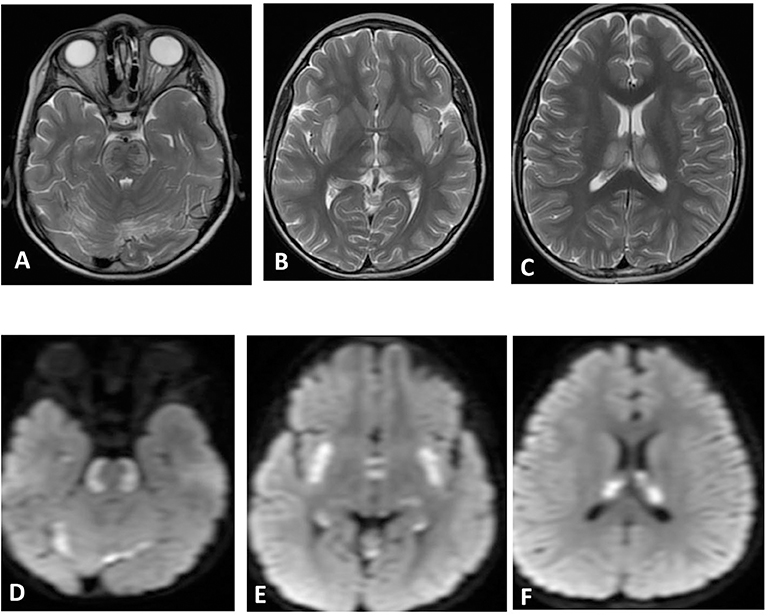

A total of 14 patients with ANEC were identified; two patients were excluded due to the inability to meet the ANEC radiological criteria. Patients' ages ranged from 10 months to 6 years (mean 30.92 months, median 22 months, standard deviation 20.63). Nine patients (75%) were female. All patients presented with preceding febrile illness in the form of upper respiratory tract infection (URTI) symptoms, or gastrointestinal symptoms in the form of vomiting or diarrhea, and altered level of consciousness. Seizures were the initial presentation in eight cases (66.7%). Brain imaging was carried out using Axial, Sagittal, and Coronal T1,T2, FLAIR, diffusion, and susceptibility weighted images which showed characteristic high signal intensity on axial T2 and FLAIR with variable degree of involvement of both thalami in all cases. Diffusion restriction was also seen, while the susceptibility sequence showed dark signal intensity with blooming, indicating hemorrhagic changes. Out of 12 patients, five (41.7%) had brainstem involvement. Follow up brain MRIs were done 2–3 months after the initial presentation, which showed signs of improvement on 33.3%, and 66.7% (n = 8) showed no signs of improvement. The clinical and radiological presentations are summarized in Tables 1, 2. Figures 1–4 show brain MRIs for selected patients.

Figure 3. Brain MRI. Axial T2 (A–C) and diffusion (D–F) showing swelling and abnormal high signal intensity of pons, bilateral external capsule, and subinsular cortex, as well as both thalami with diffusion restriction.